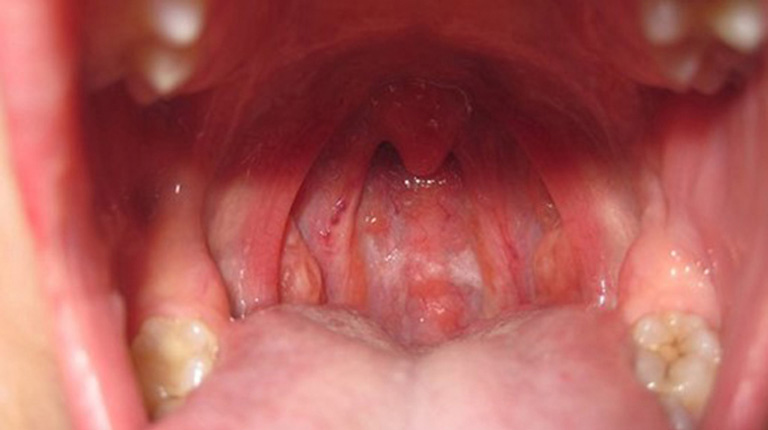

- Viêm họng cấp và mãn tính: Đây là nguyên nhân phổ biến nhất khiến niêm mạc họng bị sưng tấy, kích ứng dẫn đến cảm giác ngứa ngáy và gây ho khan.

Niêm mạc họng bị viêm là tác nhân trực tiếp gây ho ngứa cổ.